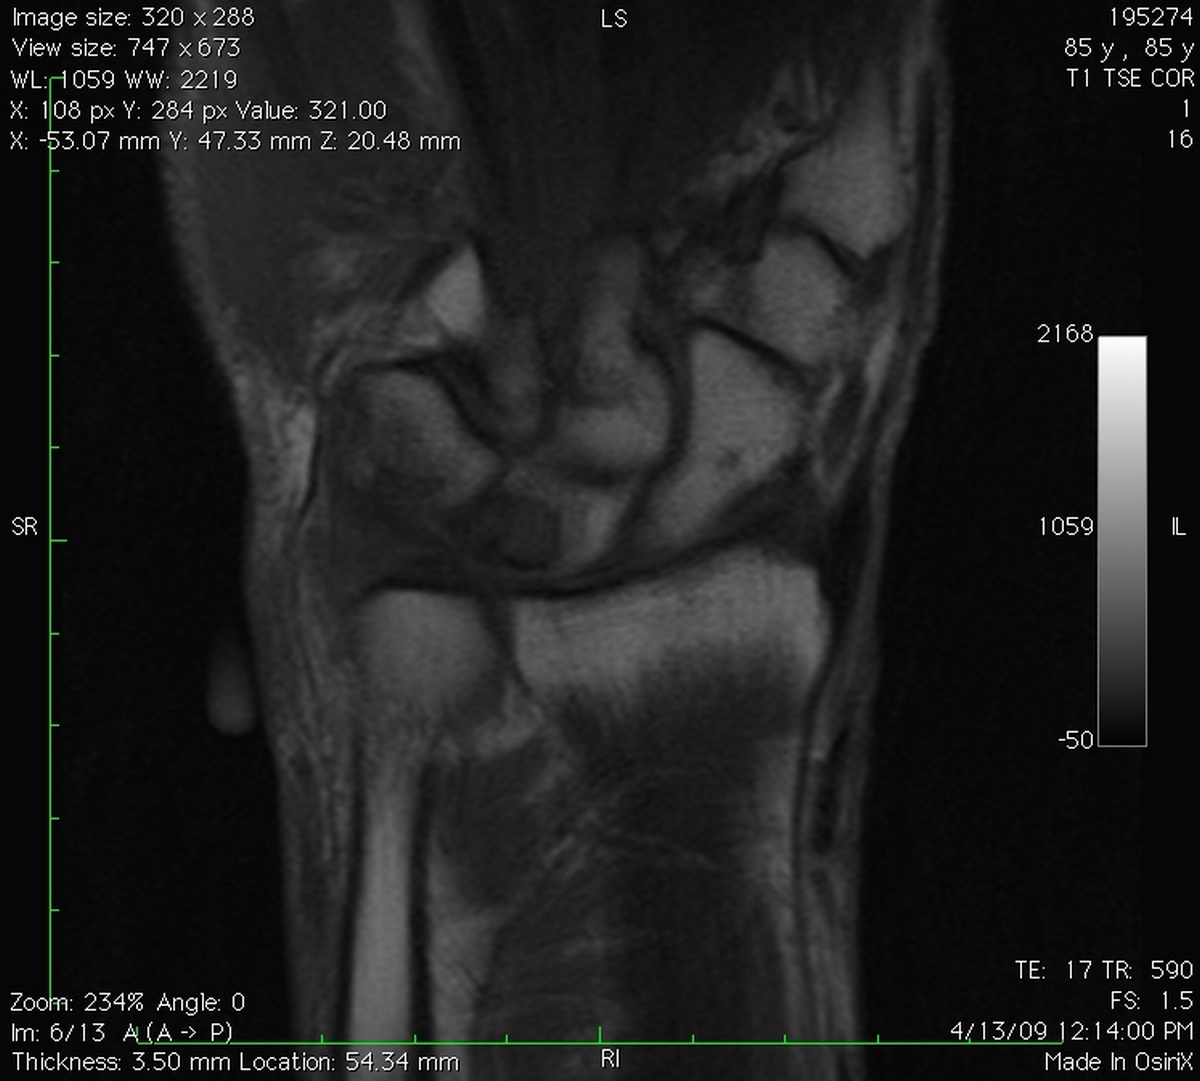

Clinical Example: Lunate Cyst

This imaging series was obtained for evaluation of a one month history of painful pronosupination in an active 85 year old man whose daily exercises include pushups.

lunate cyst